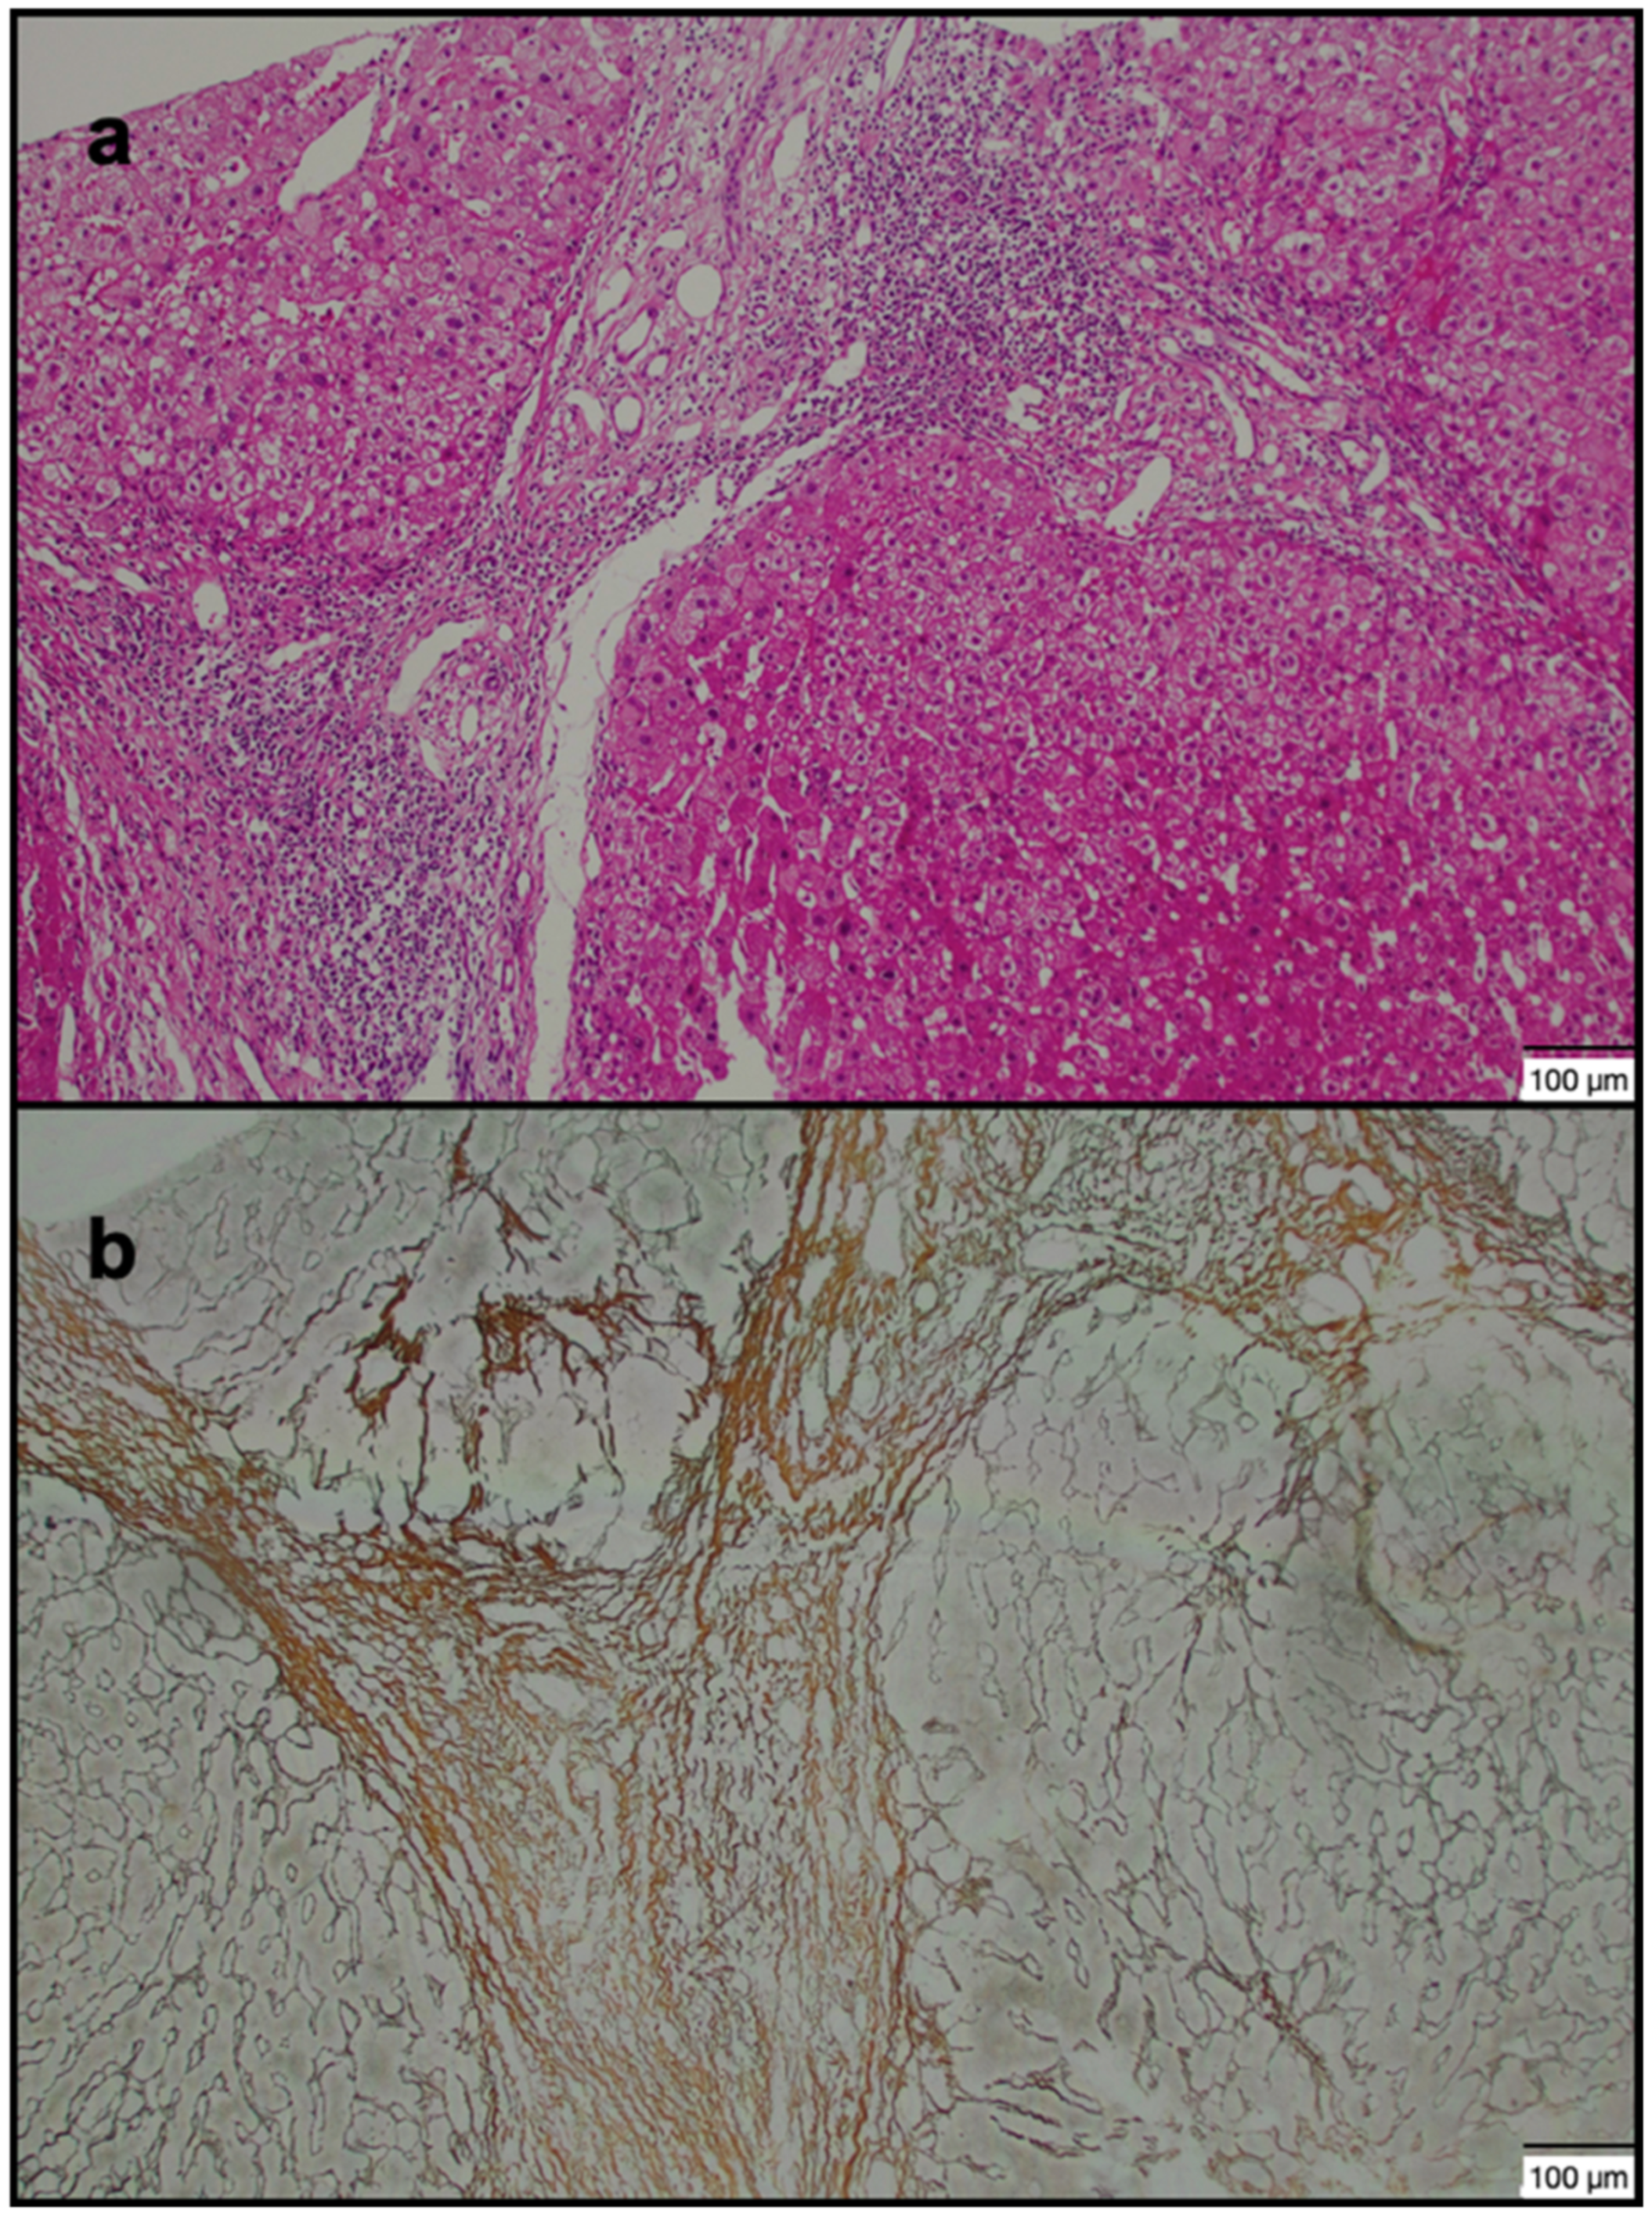

2.2. Image Analysis and Biopsy Procedure

| Fibrosis grade (≥2) | 17/40 | 20/40 | 0.501 |

| Fibrosis grade, mean (range) | 1.70 ± 1.04 (0–5) | 1.75 ± 1.06 (0–5) | 0.832 |

| Fibrosis grade (≥2) | 28/40 | 9/40 | <0.001 |

| Fibrosis grade, mean | 2.20 ± 1.09 | 1.25 ± 0.74 | <0.001 |